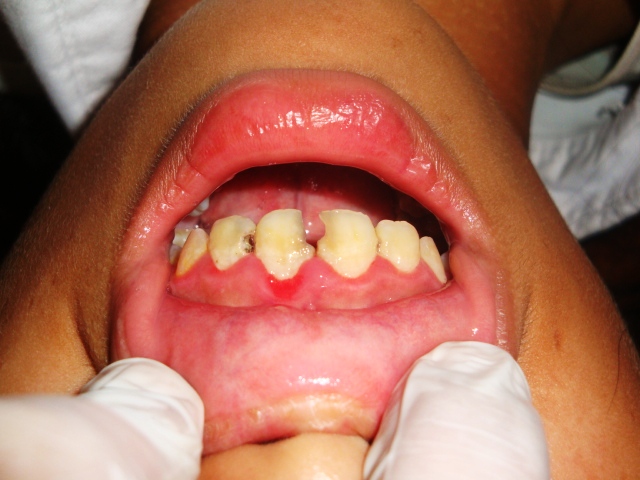

従来は無医村エリアばかりを回っていたのですが、

今回はカンボジア政府と保健省からの依頼で、

カンボジアの首都プノンペンでも行いました。

全校生徒3000人以上、国内屈指の名門校だそうです。

が、

ボロボロでした。歯が。

6年生で6歳臼歯6番が無傷な子は数えるほどで

ほとんどは残根状態です。

1年生も、Eがまともにある子は少なく、

ランパントカリエスを久しぶりに診ました。

農村部の方がまだ綺麗でした。

都市部で少し裕福なおかげで、お菓子の摂取量が半端じゃない

のに加え、水は良くないので、歯磨きは知っていても

歯磨きをしている状況はありません。

農村部では見られない、修復物が沢山ありました。